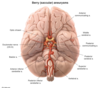

Wallenberg Sydrome

- Occurs due to occlusion of which artery?

- How does it present?

- Posterior Inferior Cerebellar Artery (PICA)

-

Presents as:

- vertigo/nystagmus

- loss of pain/temp. sensation on ipsilateral face + contralateral bofy

- Ipsilateral Horner Syndorme (ptosis, myosis, anhidrosis)

Lacunar Infarcts

- Main location

- How do they most commonly occur?

- How do they appear in the brain?

- Lenticulostriate artery

- Lipohyalinosis with small vessel occlusion

- Small fluid filled cavities